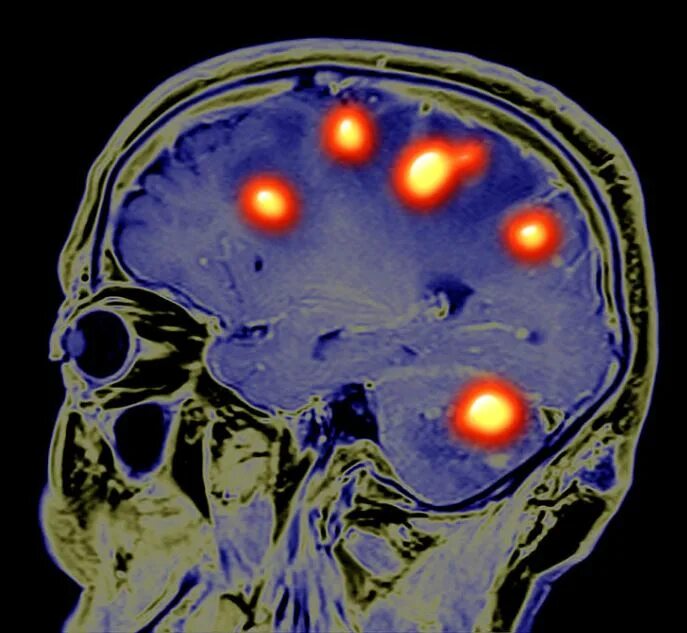

Отек мозга метастазы